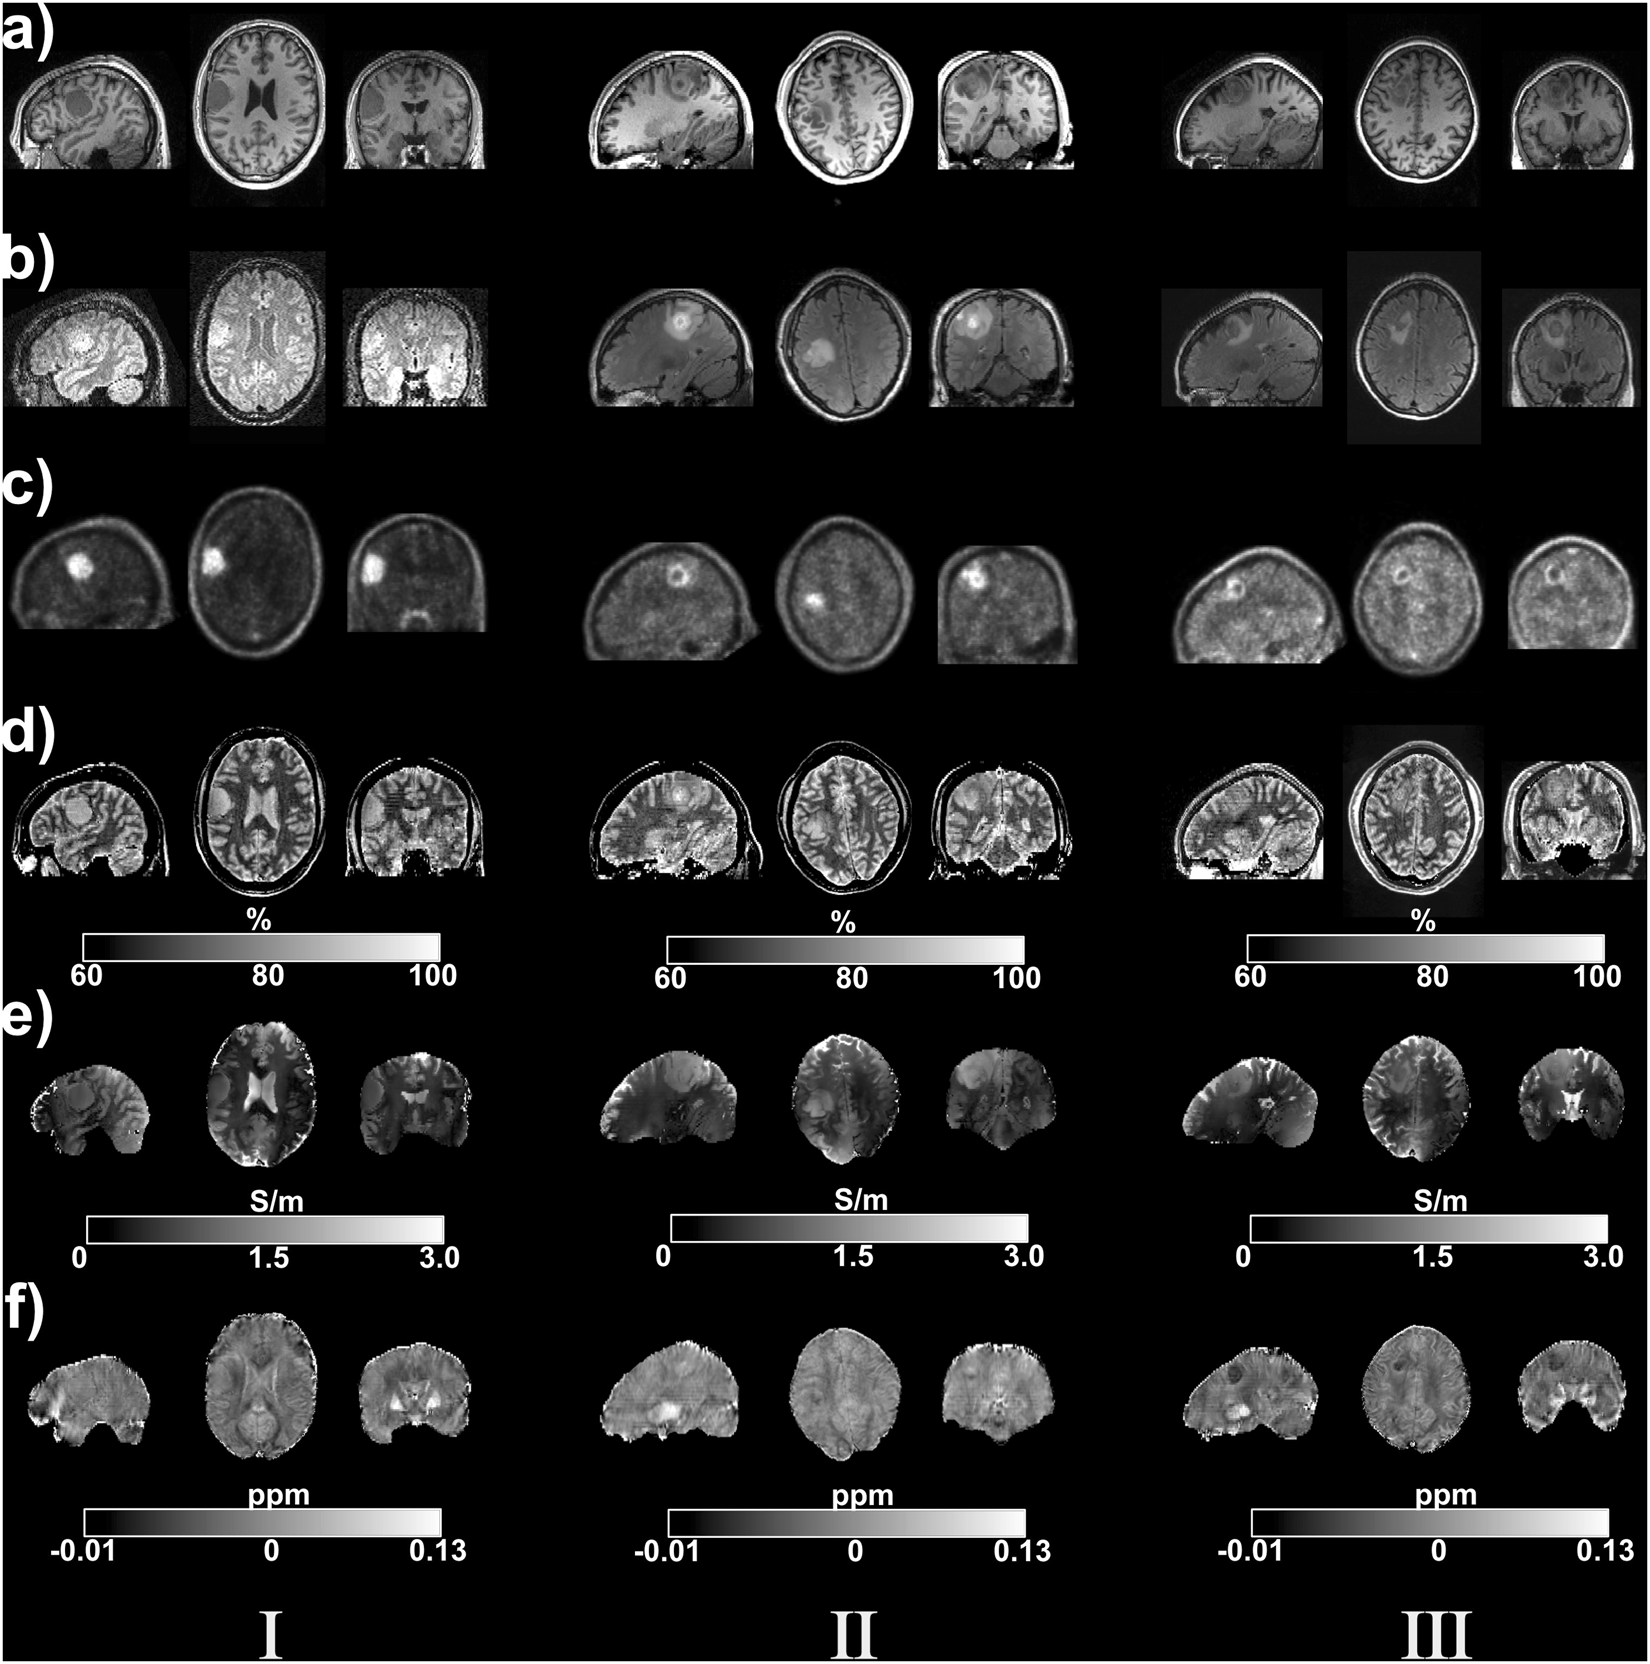

Figure 4

MR and PET images from three tumour patients. Sagittal, transverse and coronal slices through the tumours. (a) T1-weighted MPRAGE (b) proton FLAIR (c) FET-PET (d) quantitative water content (e) electrical conductivity and (f) quantitative susceptibility images. The colour bar indicates the water content in percentage, susceptibility in ppm and conductivity in S/m in the images.